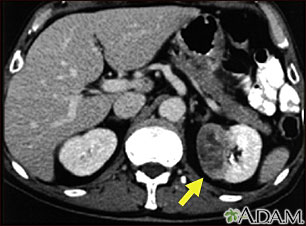

This CT scan of the abdomen shows a tumor in the left kidney (called hypernephroma, or renal cell carcinoma). It is located on the lower right side of the picture.